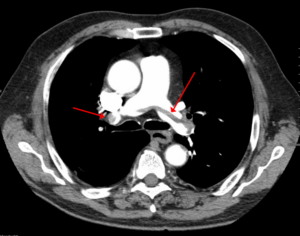

A large pulmonary embolism at the bifurcation of the pulmonary artery (saddle embolism).